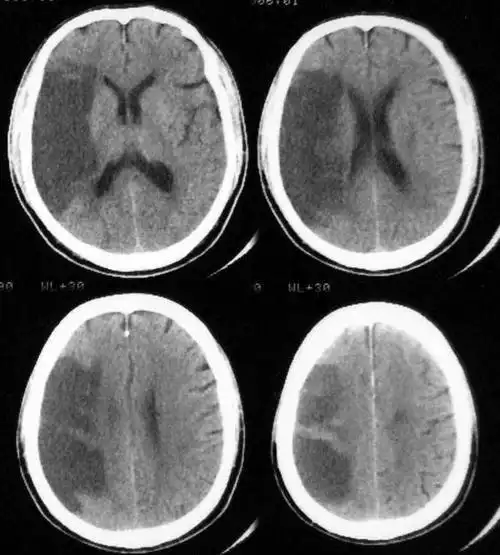

多发性腔隙性脑梗死的临床表现